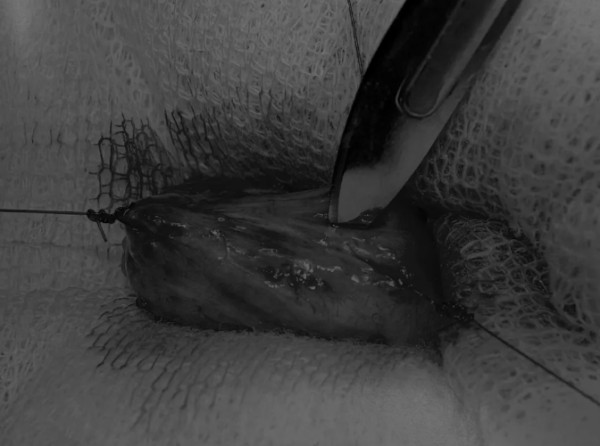

在牵引缝线之间选择血管扩张较差的区域用手术刀切开膀胱壁(图3)。在牵引缝合线之间用手术刀在血管不良的区域做切口。切开膀胱壁后,膀胱内的手术可按手术方案实施,例如取出结石(图4)。

图3 避开主要的膀胱血管,做一个尽可能小的切口

切口可以在膀胱背侧或腹侧进行,避免对大血管的损伤。